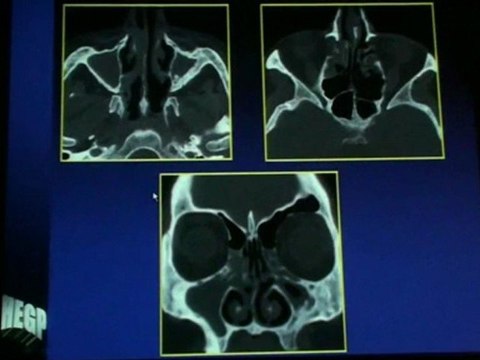

Get the facts on Sinusitis with this 100%-accurate animated video. Part of Focus Apps' Understanding Disease: Respiratory Disease series, the Sinusitis app describes the anatomy of the four types of sinuses: maxillary, frontal, sphenoidal, and ethmoidal. Sinusitis is the inflammation of the sinuses. Symptoms of sinusitis include fever, weakness, cough, and congestion of the nose, in addition to postnasal drip. Infections can be bacterial, fungal, viral, allergic, or related to an autoimmune disease. Explore the pathophysiology, symptoms, treatments, and management of sinusitis.